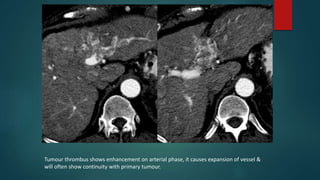

Tumour thrombus shows enhancement on arterial phase, it causes expansion of vessel &

will often show continuity with primary tumour.